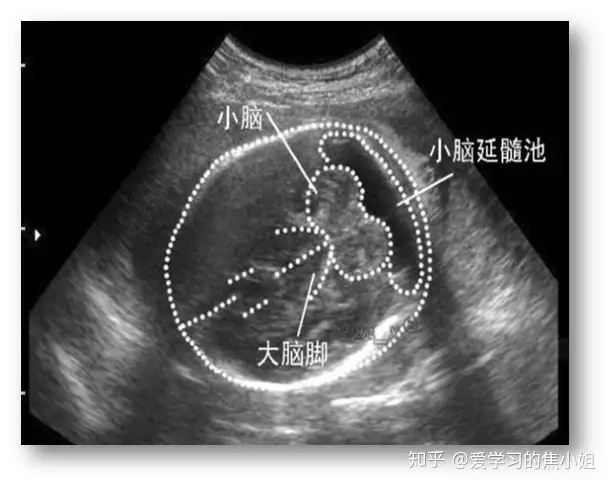

六、小脑延髓池扩大

小脑延髓池是小脑和延髓周边的空隙,它分为位于小脑和延髓后表面之间的小脑延髓池和位于小脑和延髓外侧之间的小脑延髓池,中间有脑脊液。

正常:≤10mm。小脑延髓池扩大:直径10mm以上。持续增宽会导致脑积水。